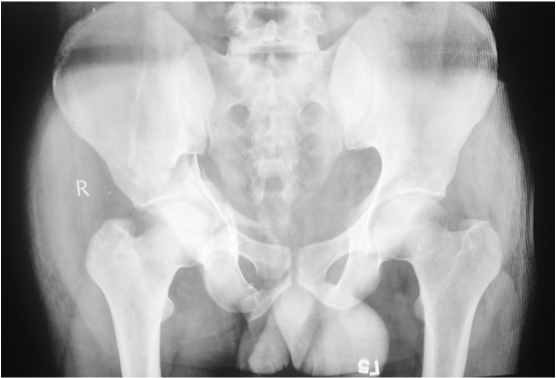

Various kinds of articular cartilage injuries were noted like free intra-articular fragments, chondral fissures on the cartilage of the femoral head and impacted fractures on the acetabular surface were observed in seven fractures operated by the Kocher-Langenbeck approach. Removal of intraarticular fragments required redislocation of the hips in five patients. Patients operated by ilioinguinal approach had limited visualization of the intra-articular injury and cartilage injuries could not be observed (Figure 3). Postoperatively, immobilization or traction was not used. Non weight bearing exercises were commenced within one week of the operation. Partial weight bearing was allowed after eight weeks and full weight-bearing was allowed twelve weeks after the operation. Low molecular weight heparin was used as prophylaxis against deep venous thrombosis in all patients. No routine prophylaxis against heterotopic ossification was used.

Figure 3 Postoperative radiograph of the same patient as in Figure 1 operated by the Ilioinguinal approach showing anatomical reduction.